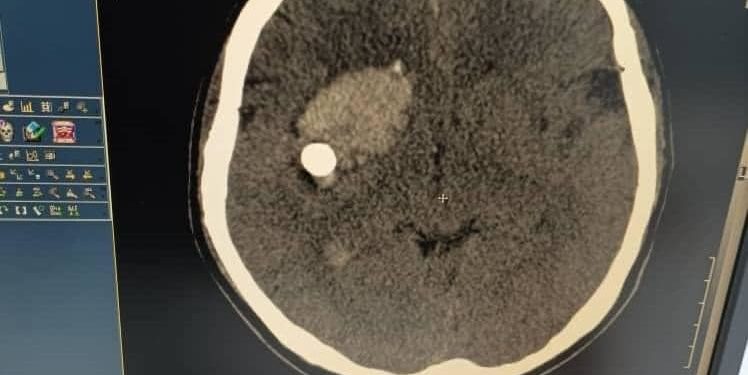

Кечээ, 9-февралда Жалал-Абад облустук клиникалык ооруканасынын нейрохирургдары мээге татаал операция жасашты. Бул тууралуу Саламаттыкты сактоо министрлигинен билдиришти.

Маалыматка караганда, медицина илимдеринин кандидаты, аймактык оорукананын нейрохирургия бөлүмүнүн башчысы Абдибайит Идирисов жана анын командасынын аркасы менен бейтаптын өмүрү сакталган. Бейтап башынын ачык жарасы менен келип түшкөн. Оң жактагы маңдай бөлүкчөсүндө мээге ок кирип кеткен. Операция ийгиликтүү аяктаган. Бейтаптын абалы туруктуу деп бааланууда.